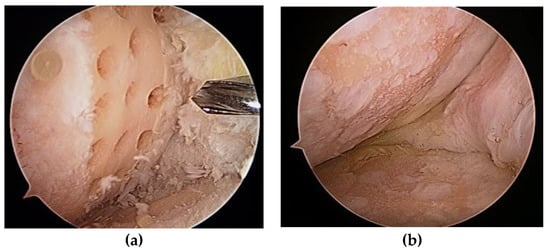

AMIC requires an open procedure to attach the collagen matrix to the cartilage defect (Figure 5). Even a small defect in articular cartilage needs a large incision for the AMIC procedure, which can delay patient recovery.

Figure 5. (a) Cartilage defect, (b) after defect preparation, (c) membrane-covered defect, and (d) second-look arthroscopy 2 years later. Image courtesy of Prof. Sung-Hwan Kim.